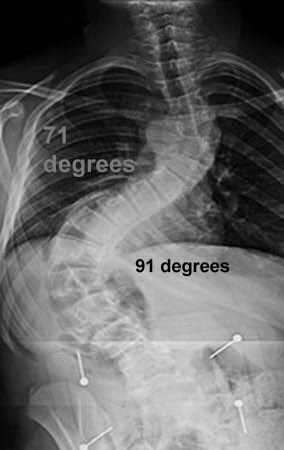

للتعامل مع حالات #الجنف #Scoliosis